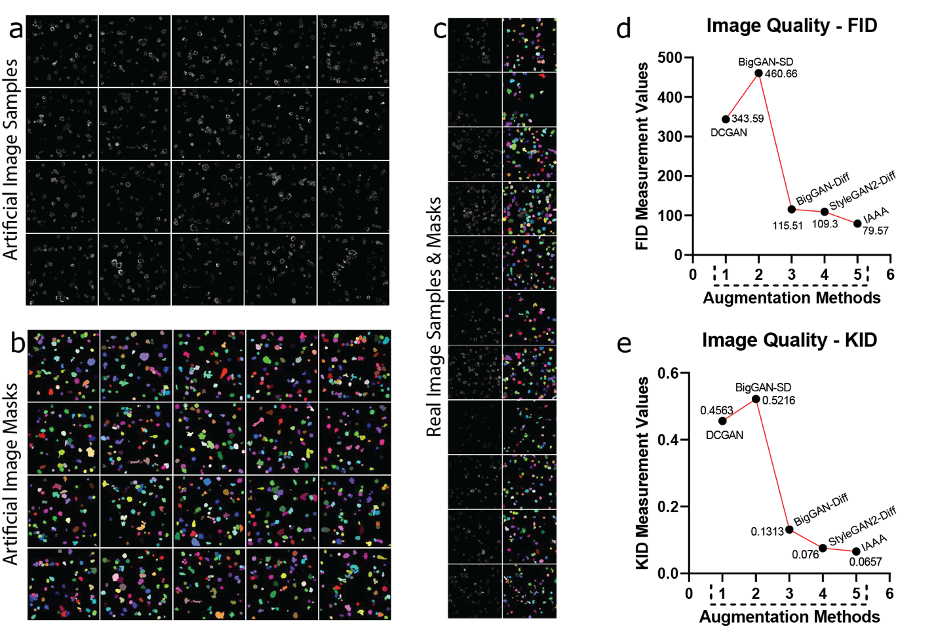

The results of the image generation are presented in Fig. 3. Due to the simplified nature of SCO, most methods perform well in producing strong artificial SCO images. Fig. 3a–b shows a sample of SCO images and their associated masks that were generated by our method for the CAR-T/NK dataset. Respectively, Fig. 3c–d shows a sample of original SCO images with their associated masks. In all the images, the original images corresponded to the zoomed-in regions. From these images, the proposed method produces outputs with a great likeness to the original SCOs.

Refer to caption

Figure 3: Representative image generation using SCOs. The (a) and (b) represent the artificial images and their masks generated by our method. The (c), and (d) represent reference (real) images which are accompanied by their associated masks. We zoom into different regions of the images for better visibility of SCOs. The FID and KID scores of SCOs, are presented in (e), and (f) using the CAR-T/NK dataset. For comparison, the quality of images from IAAA is measured against four GAN methods (DCGAN, BigGAN-SD, BigGAN-Diff, and StyleGAN2-Diff).

To evaluate the quality of the images, we use the Fréchet Inception Distance (FID) and the Kernel Inception Distance (KID), which have shown better support for smaller datasets [3]. In other words, we answer how much applying different augmentation policies affects the quality of SCOs. The average scores are reported with numerical values and are computed over three random sets of sample generation.

For the FID scores (Fig. 3e), the results show that our method performs competitively compared to existing models. The best-performing GAN model is StyleGAN2-Diff, which is outperformed by 22.95 using the proposed method with the CAR-T/NK data. The KID scores (Fig. 3f) show that the proposed method has a higher score than StyleGAN2-Diff by 0.01105 using the CAR-T/NK data. This shows that the controlled environment was successful in the generation of SCOs and IAAA preserves the original traits of the natural cells found in the raw data.

The results to produce MCOs using the CAR-T/NK dataset are presented in Fig. 4. Similar to the SCO, samples are provided for observation. Fig. 4a–b shows a sample of MCO images and their associated masks that were generated by our method for the CAR-T/NK dataset. Respectively, Fig. 4c–d shows a sample of the original MCO images with their associated masks. In all the images, the original images corresponded to the zoomed-in regions. The results show that the controlled environment was again successful in generating new MCOs while simultaneously preserving the traits found within the original cells.

Figure 4: Representative image generation using MCOs. The (a) and (b) represent the artificial images and their masks generated by our method. The (c), and (d) represent reference (real) images which are accompanied by their associated masks. We zoom into different regions of the images for better visibility of MCOs. The FID and KID scores of MCOs are presented in (e), and (f) using the CAR-T/NK dataset. For comparison, the quality of images from IAAA is measured against four GAN methods (DCGAN, BigGAN-SD, BigGAN-Diff, and StyleGAN2-Diff).

For the FID scores (Fig. 4e), the results show that our method greatly outperforms the existing models across all parameters. The FID score of the proposed method surpasses the best-performing GAN model StyleGAN2-Diff by 68.41 within the CAR-T/NK dataset. For KID scores (Fig. 4f), the data shows the proposed method has a better generation quality for MCOs. The best performing GAN model is again StyleGAN2-Diff, which is outperformed by 0.04365 by our method within the CAR-T/NK dataset. The evaluation scores show the difficulty of generating naturalistic MCOs for GAN models due to the many variables that result in cell clustering and adhesion.

The results of the creation of complete CAR-T/NK cell images are presented in Fig. 5. We also provided more samples with higher resolution in the supplementary (Supplementary Figures S1–S19 show generated and real images, SCO and MCO samples, augmentation examples, and final image comparisons across the evaluated datasets). Fig. 5a–b shows a representative set of final images and their associated masks that were generated by our method for the CAR-T/NK dataset.

Figure 5: Representative image generation by MCOs using the CAR-T/NK dataset. The (a) and (b) represent the artificial images and their masks generated by our method. The (c) represents reference (real) images which are accompanied by their associated masks. The FID and KID scores are presented in (d), and (e) using the CAR-T/NK dataset. For comparison, the quality of images from IAAA is measured against four GAN methods (DCGAN, BigGAN-SD, BigGAN-Diff, and StyleGAN2-Diff).

Respectively, Fig. 5c shows a set of original images with their associated masks. In all the images, the original images are corresponded to the zoomed-in regions. The results show the precise segmentation masks that our method provides and demonstrate the capability to create high-quality images over many samples.

For the FID scores (Fig. 5d), the proposed method consistently outperformed the best-performing GAN method, Style- GAN2, by 29.73 with the CAR-T/NK dataset. The results remained consistent with the KID values (Fig. 5e), with the proposed method outperforming StyleGAN2 by 0.0103 using the CAR-T/NK dataset. The FID and KID scores demonstrate that similar to SCOs and MCOs, the IAAA could outperform GAN models to generate high-quality augmented images.